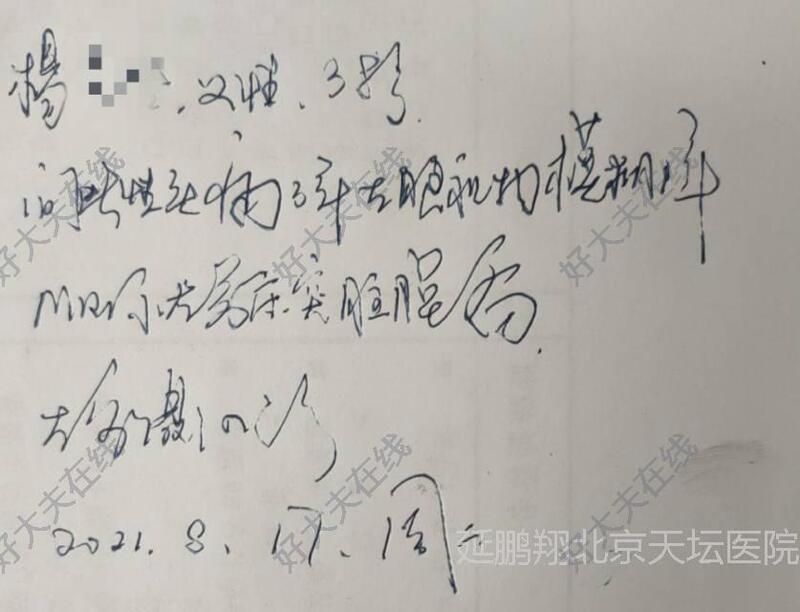

患者女性,38岁。间断性头痛3年左眼视力模糊1年。核磁显示左侧前床突脑膜瘤。